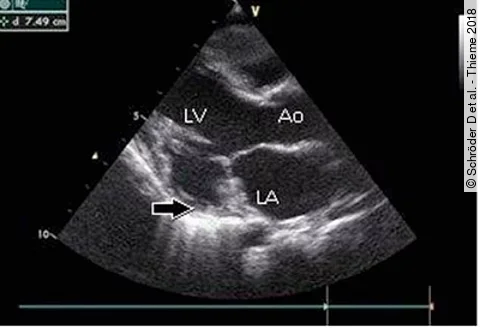

Baby mit HerzfehlerWarum auch die Mütter auf ihr Herz achten sollten

Treten beim Nachwuchs kongenitale Herzfehler auf, ist das für die Eltern meist ein beunruhigender Zustand. Auch wenn beide Elternteile als gesund gelten, sollte sich die Mutter mit ihrer Herzgesundheit befassen. Denn: Hat der Nachwuchs Herzfehler, erhöht sich das Risiko für kardiovaskuläre Probleme der Mutter in den kommenden Jahren, wie diese…